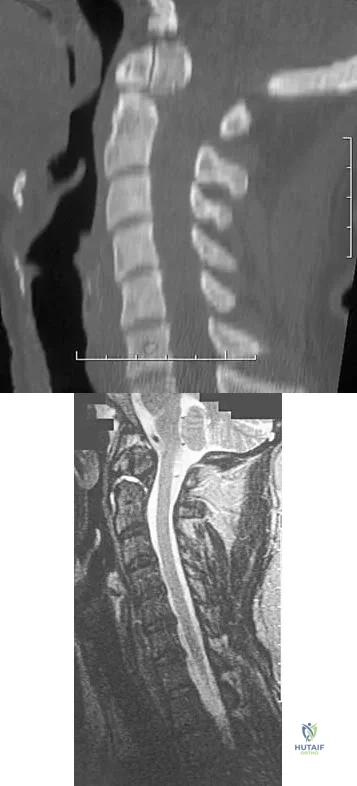

Figure 7 shows the radiograph of a 64-year-old man who has neck pain and weakness of the upper and lower extremities following a motor vehicle accident. Examination reveals 3/5 quadriceps and 4/5 hip flexors but no ankle dorsiflexion or plantar flexion. His intrinsics are 1/5, with finger flexors of 3/5. He is awake, alert, and cooperative. Management should consist of

A 42-year-old woman reports that she has low back pain and had a transient loss of consciousness after falling off a horse. She denies having neck pain but notes that she was involved in a motor vehicle accident 2 years ago and had neck pain at that time. Examination reveals full range of motion of the neck and no localized tenderness. The neurologic examination is normal. A lateral radiograph of the cervical spine is obtained. Figures 41a and 41b show CT and MRI scans. What is the most likely diagnosis?